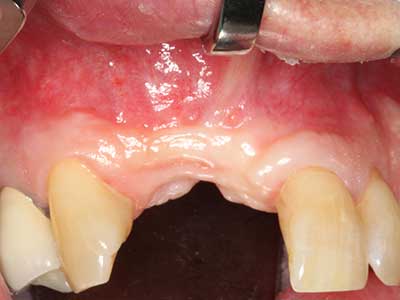

Indicazione: terapia parodontale

Le malattie parodontali marginali sono la causa più probabile di estrazioni in età avanzata. Queste malattie sono provocate anzitutto dalla colonizzazione batterica della tasca gengivale, che causa infiammazione seguita da perdita del parodonto. La formazione di biofilm sottogengivali e concrezioni è un fattore eziologico significativo per l'atrofia ossea marginale, pertanto la loro rimozione è una fase importante del trattamento (Drisko 2014, Plessas 2014).

La fase iniziale e quella chirurgia della procedura sono diverse nel trattamento della parodontite marginale. Oltre a fornire istruzioni sull'igiene orale e a motivare i pazienti, entrambe le fasi devono includere una pulizia adeguata della superficie delle radici. Nel contesto rigenerativo in genere è preferibile disporre di un accesso aperto. È possibile pulire la superficie delle radici mediante piezochirurgia utilizzando raccordi specifici; per raggiungere zone di difficile accesso, come le forcazioni, si utilizzano strumenti con diverse curvature. L'irrigazione integrata nel sistema elimina dalla tasca le concrezioni staccate e i batteri. Sistemi specifici, come Piezomed, includono anche un ritorno dell'applicazione per minimizzare l'ablazione dello smalto. Più il parodonto aderisce al dente, maggiore sarà la riduzione della sostanza ablata.